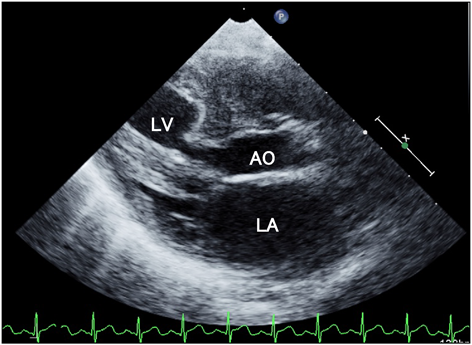

Fig. 4 Left ventricular outflow obstruction in hypertrophic obstructive cardiomyopathy

A 6-month-old girl with localized hypertrophic obstructive cardiomyopathy and congenital mitral regurgitation presented with cardiogenic shock. This long-axis echo view shows significant obstruction in the mid-portion of the left ventricular outflow. As the anterior leaflet of the mitral valve is situated between the inflow and outflow of the left ventricle, mitral valve replacement was considered as a surgical option to relieve obstruction. LA: left atrium; LV: left ventricle; AO: ascending aorta